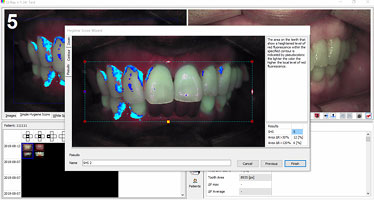

원인을 제대로 찾지 못하면 치료가 길어집니다. AI 기술이 적용된

첨단 장비를 통해 잇몸병의 원인을 꼼꼼하게 분석합니다.

AI 리포트를 활용해 잇몸병 원인에 맞는 예방 및 치료 계획을 세웁니다.